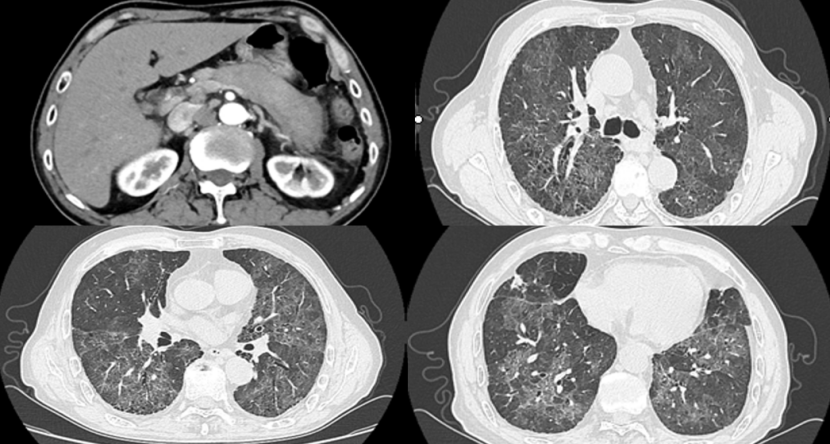

1CMV肺炎:单纯的CMV肺炎比较罕见,笔者中心1000多例移植患者仅有2例发生CMV肺炎。其中1例患者肾移植术后1月余,发热1天。影像学可见双肺弥漫性病变,多发结节(图12)CMV肺炎进展及恢复速度都很快(图13)

12  患者影像学表现

13  患者治疗前后胸部CT变化